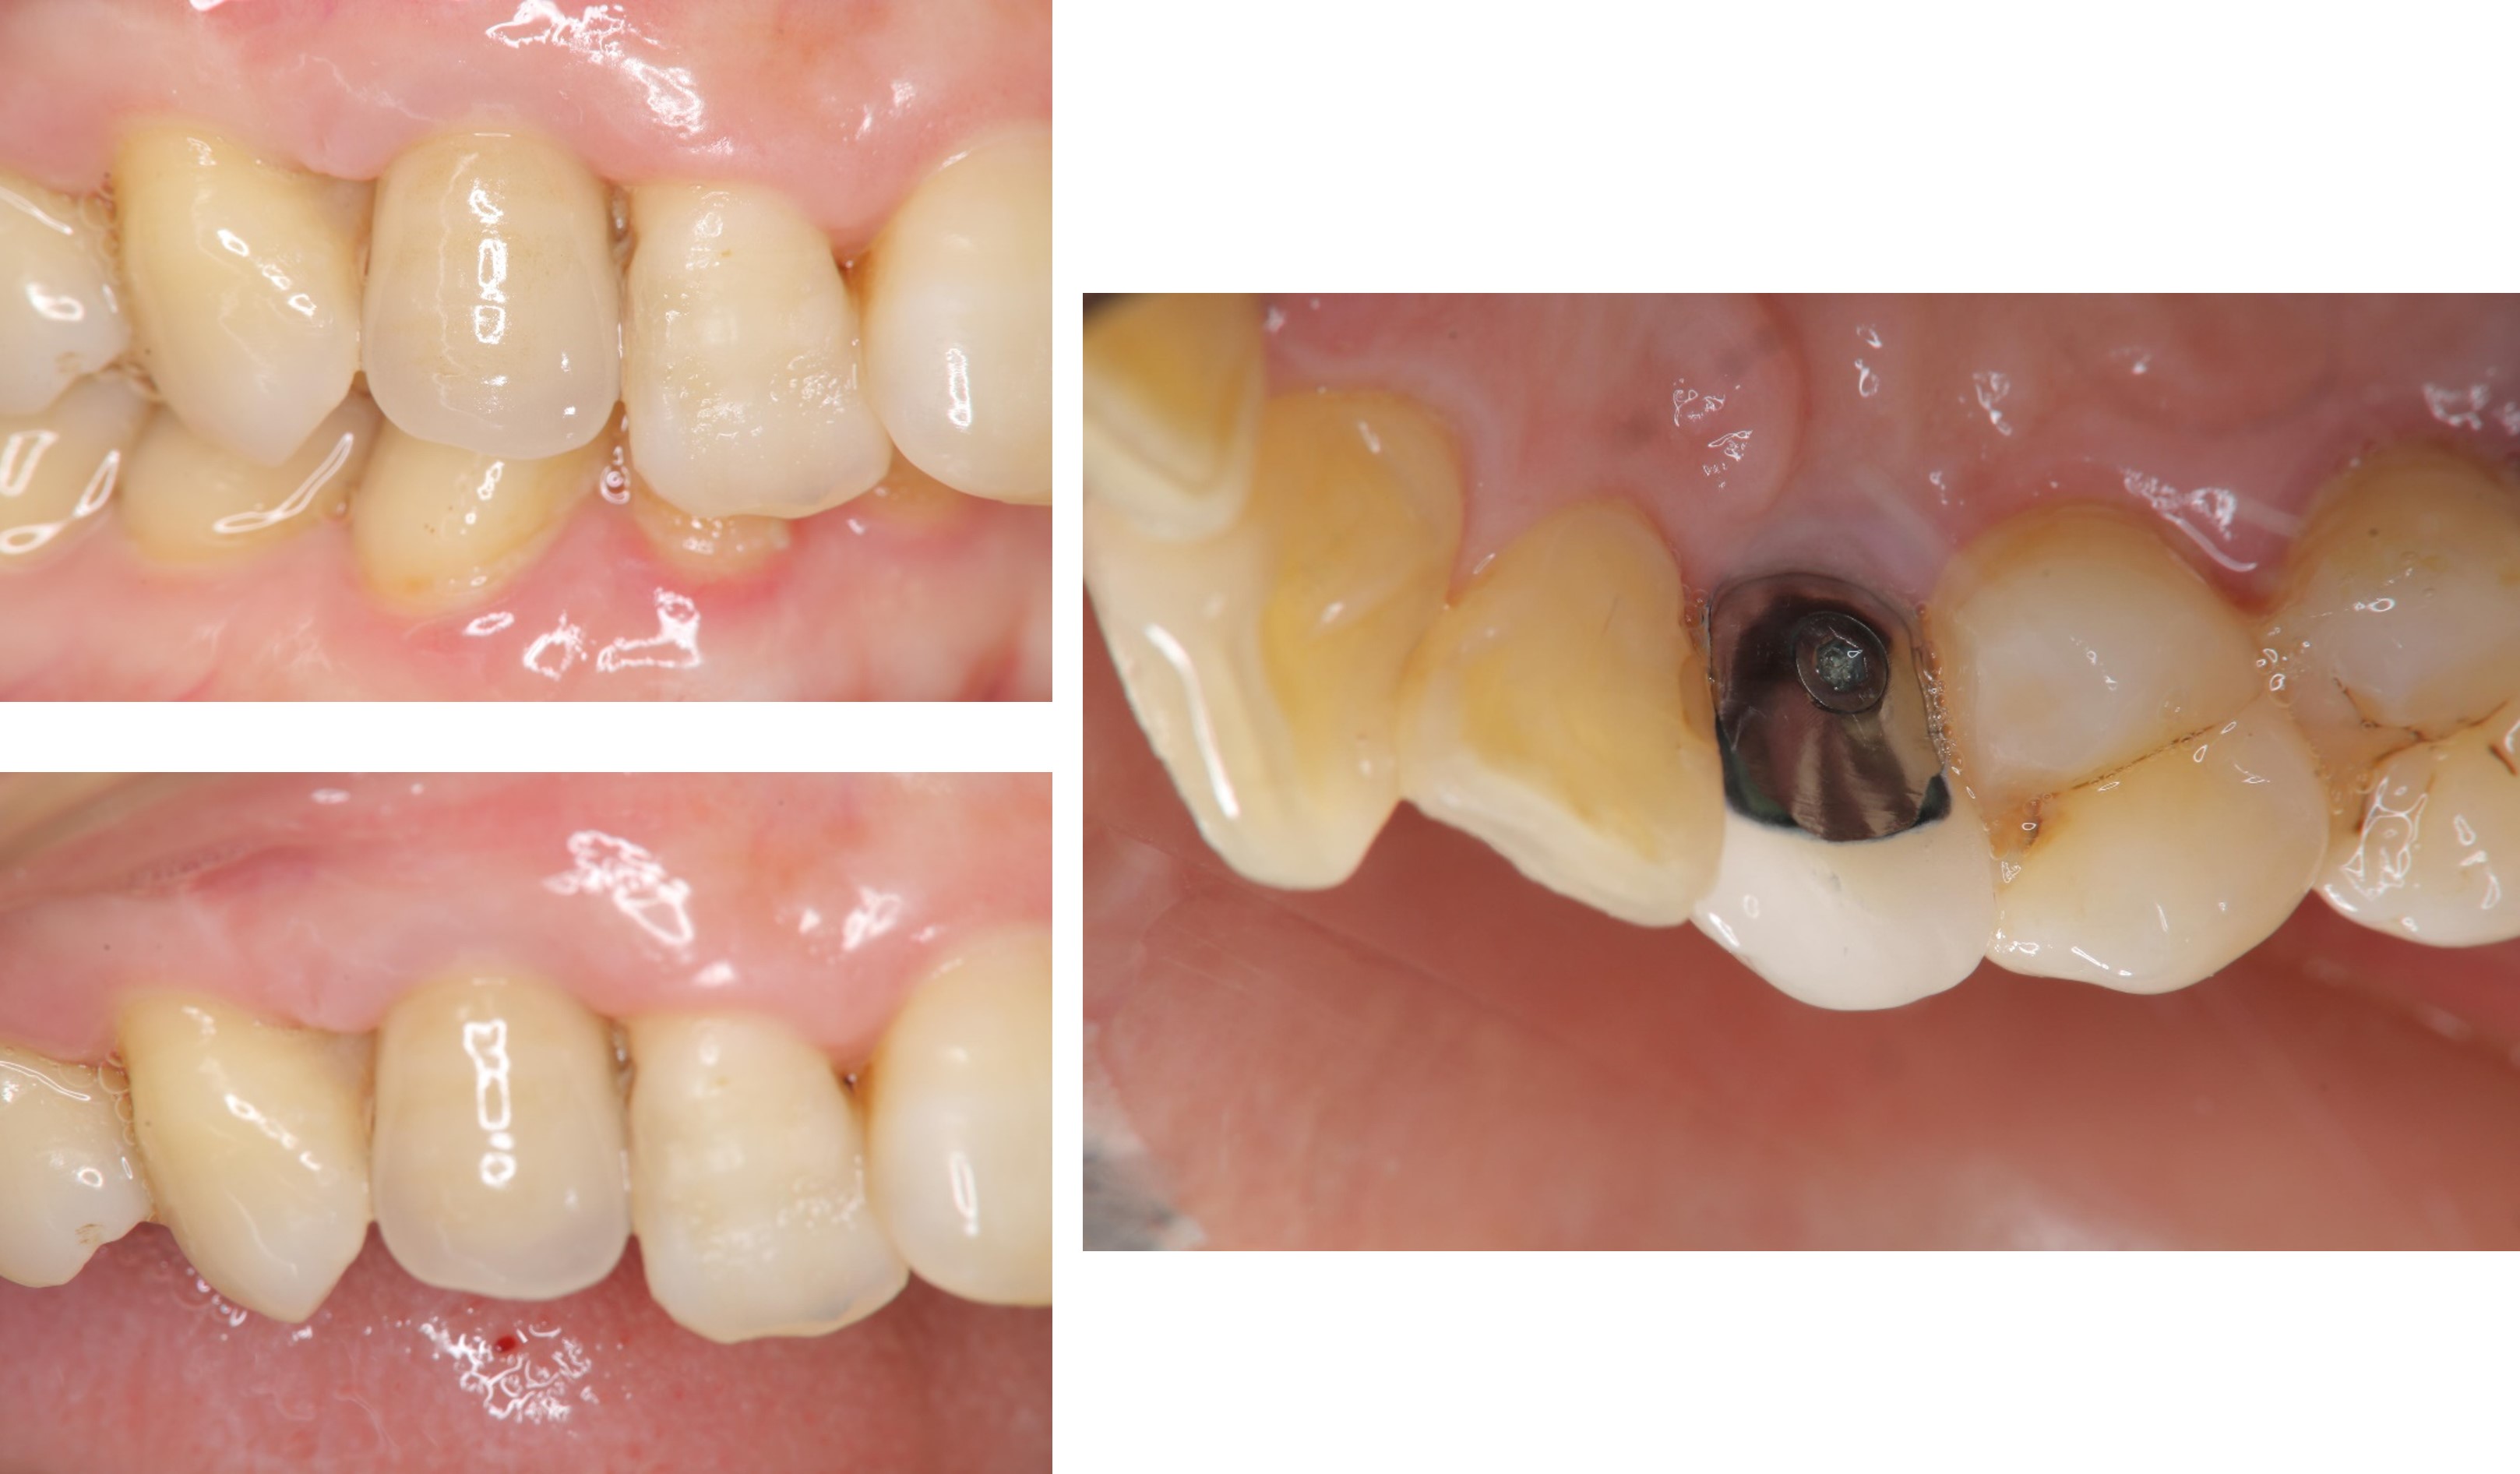

舌側螺絲固位冠

治療後,咬合牙周適應良好

治療後,密合度良好